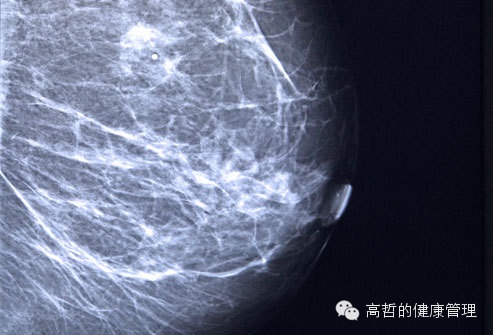

乳腺癌和乳腺x光片

乳腺癌发现的越早,治疗越容易。乳腺X射线可以在肿块未长大之前就发现。美国癌症研究所建议女性从40岁开始每年都应该做一次乳腺X射线。美国预防服务工作组建议50—74岁的女性每两年检查一次,考虑到定期检查的利益关系,每个女人在50岁前都应该与自己医生交谈,哪一种筛查更利于她自己。